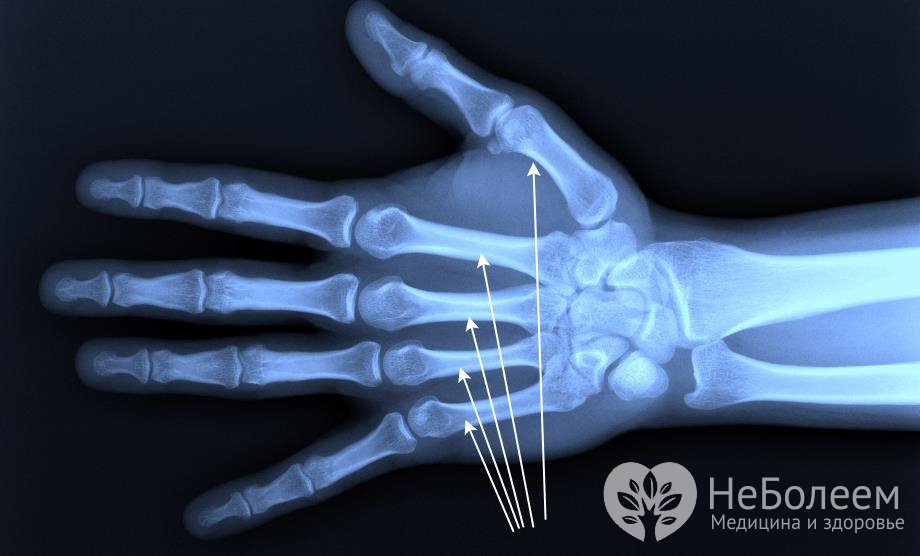

Наиболее распространенными травмами являются переломы пястной кости, основания, диафиза и фаланг пальцев. Чаще всего встречается перелом первой и пятой пястных костей. Травма может быть нанесена прямым ударом о тупой предмет.

В редких случаях возникают переломы второй, третьей и четвертой пястных костей. Обычно такой перелом происходит из-за травмы кисти или удара кулаком о тупой предмет.

Перелом пястной кости у основания бывает нескольких типов: внутрисуставный, внесуставный и поперечный. Симптомами являются боль в области перелома, отек, невозможность сгибания пальца, а при прощупывании места перелома усиливается болевой синдром. Переломом Беннета называется травма, при которой есть осколок треугольной формы, а также вывих в сторону лучевой кости. Осложненный перелом с вывихом называется переломом Роланда. Точный диагноз устанавливается с помощью рентгенографического обследования.

Лечение начинается с рентгенограммы и накладывания гипсовой повязки от предплечья до основания пальцев. В некоторых случаях требуется оперативное лечение и фиксация пальцев с помощью спиц.

Перелом фаланг пальцев происходит при сильном прямом или непрямом ударе пальца. Такой перелом имеет несколько типов: поперечный, винтообразный, оскольчатый, внутрисуставный и внесуставный. Симптомами являются боль, припухлость руки, отек пальца, болезненные ощущения при разгибании кисти. При первом осмотре наблюдается деформация пальца.